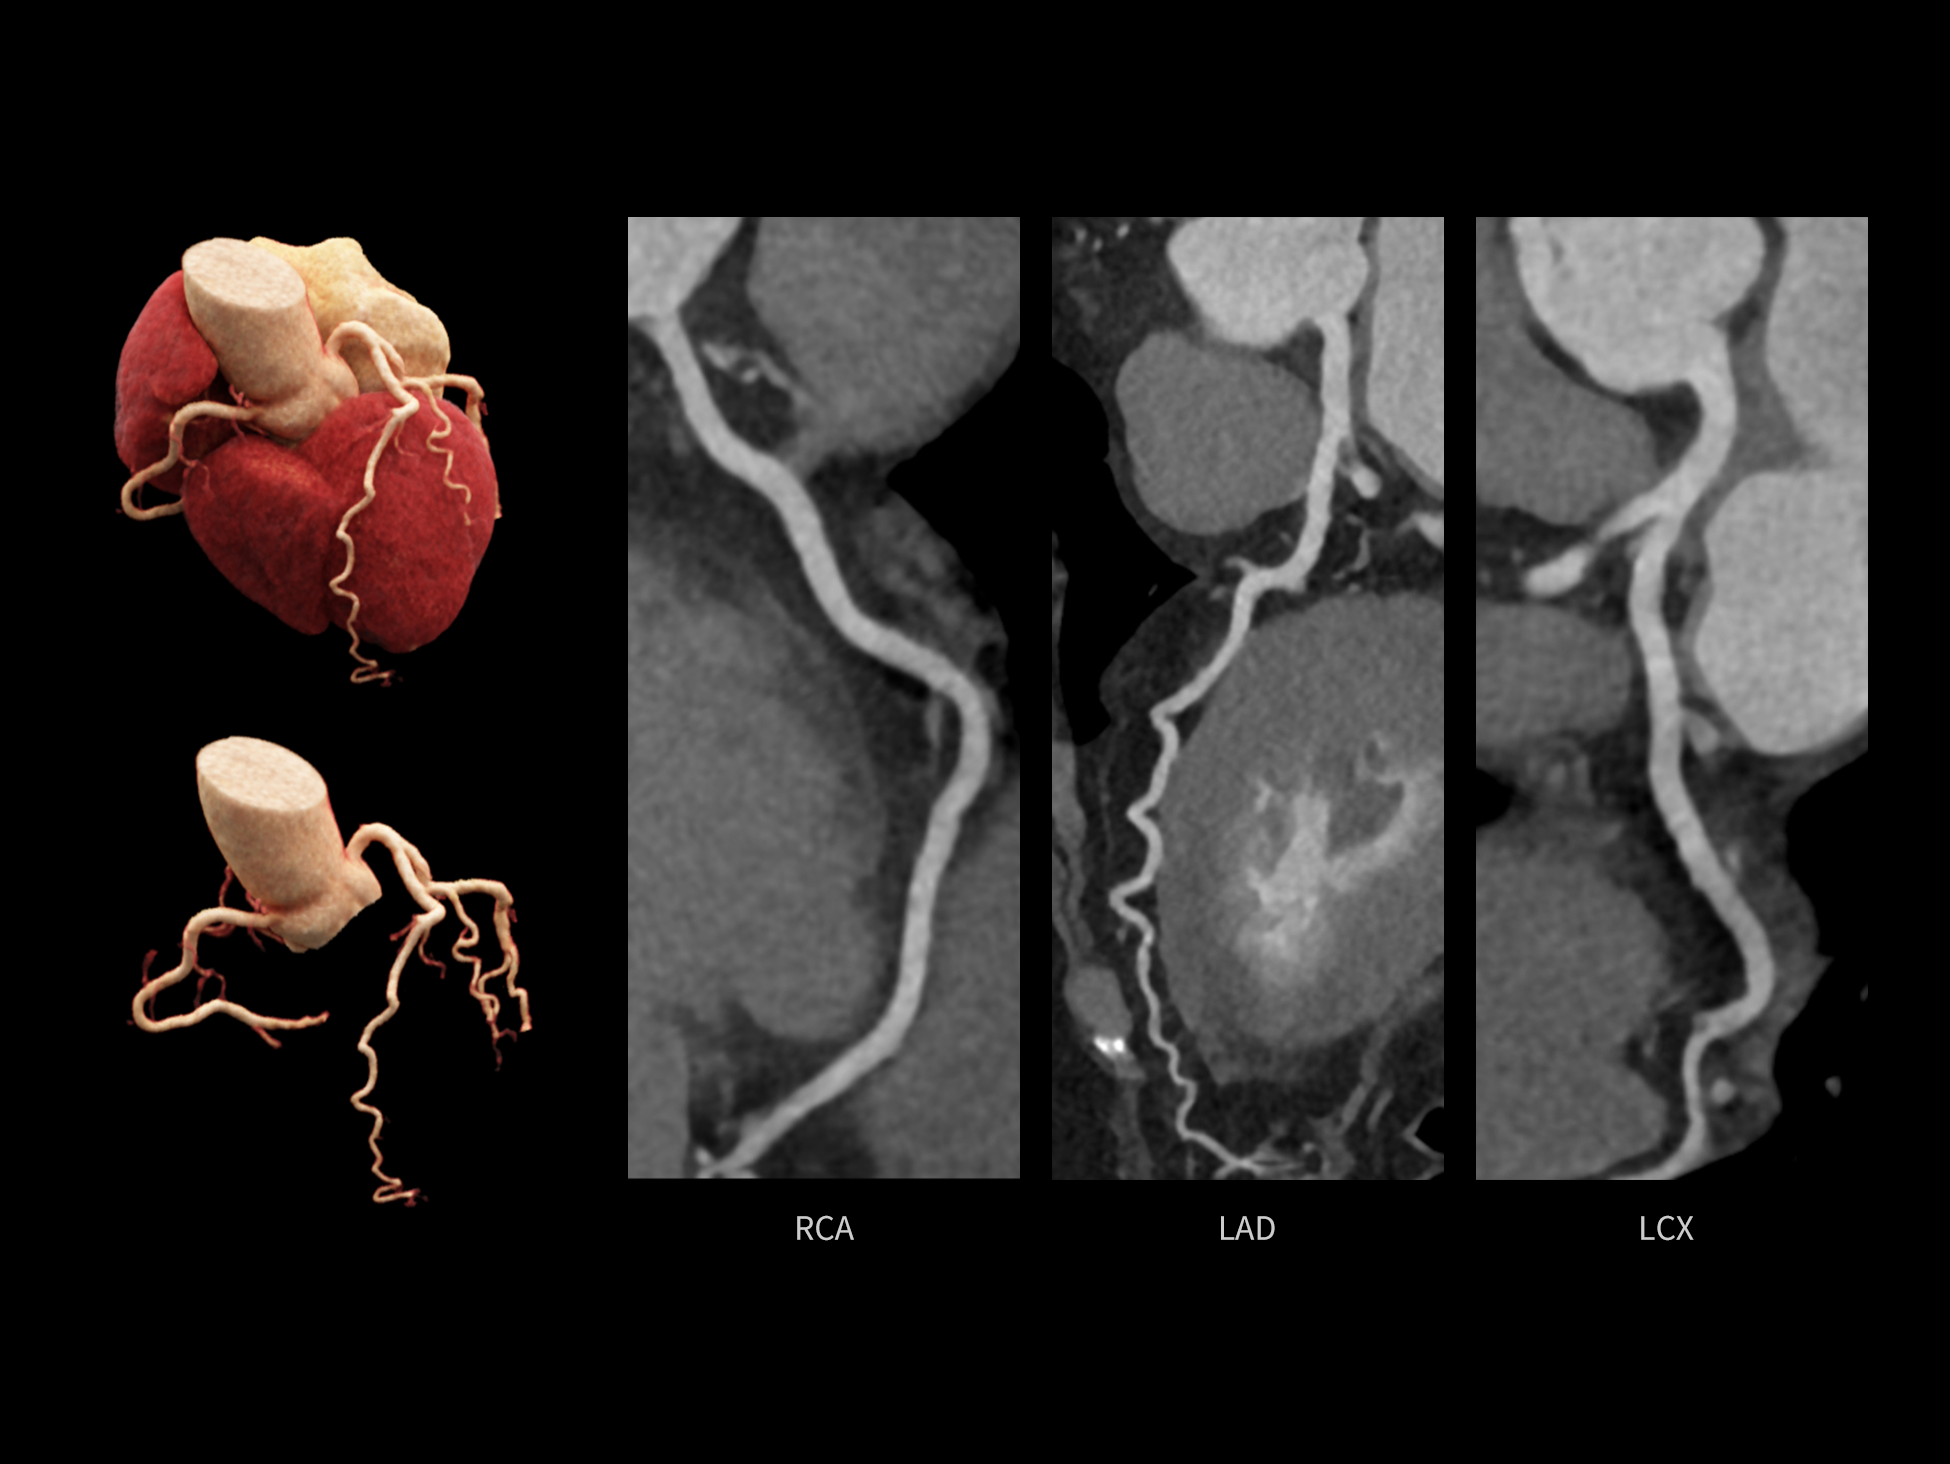

全时心脏

uCT SiriuX® 依托16cm超宽探测器与双源能谱技术,实现真正意义上的全身高清能谱成像。单次扫描同步获取灌注、能谱等多维定量参数,精准解析组织特性与病灶成分,为临床决策提供更深层次的诊断依据。

能谱成像可揭示丰富的物质与能量信息,其临床价值的充分释放有赖于完善高效的后处理分析平台。uCT SiriuX® 提供全面能谱高级分析工具,覆盖心血管、肿瘤、神经、骨科等多类临床场景。平台支持动脉增强分数分析(AEF)、细胞外容积分析(ECV)、肿瘤同源性分析、肺栓塞分析、骨髓水肿分析等多项评估,并提供多达10种基物质对成像,为精准诊断与科研探索提供坚实支撑。